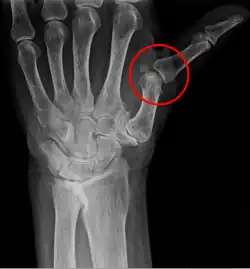

A subluxation of a joint is where a connecting bone is partially out of the joint.[5] In contrast to a luxation, which is a complete separation of the joint, a subluxation often returns to its normal position without additional help from a health professional.[6] An example of a joint subluxation is a nursemaid's elbow, which is the subluxation of the head of the radius from the annular ligament. Other joints that are prone to subluxations are the shoulders, fingers, kneecaps, ribs, wrists, ankles, and hips affected by hip dysplasia. A spinal subluxation is visible on X-rays and can sometimes impinge on spinal nerve roots, causing symptoms in the areas served by those roots. In the spine, such a displacement may be caused by a fracture, spondylolisthesis, rheumatoid arthritis,[7] severe osteoarthritis, falls, accidents and other traumas.